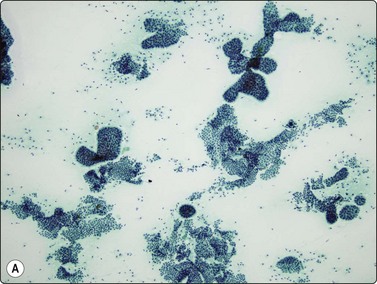

image image image

Fig. 8.28 High-grade neuroendocrine carcinoma; small cell carcinoma

(A, B) Smears showing ‘intermediate’ morphology. Loose aggregates of fragile cells with traumatization artifact and nuclear molding but some background cytoplasm (A, Pap, MP; B, H&E, HP). (C) Tissue section of resected peripheral stage 1 small cell carcinoma (H&E, HP).

image image image image image

Fig. 8.29 High-grade neuroendocrine carcinoma

Variable morphology including small cell and large cell patterns. (A) Low-power smear appearances of small cell carcinoma; (B) Higher-power examination shows some large cells with prominent nucleoli (A, H&E, LP; B, H&E, MP). (C,D) Tissue sections of resected peripheral stage 1 tumor showing areas of geographic necrosis and a predominance of large cells with prominent nucleoli (C, tissue section, H&E, LP, Inset, HP; D, tissue section, H&E, HP). (E) Positive immunostaining for chromogranin in resected specimen (E, tissue section, IPOX, HP).

Although ‘intermediate’ small cell carcinoma is no longer recognized as a separate category in international classifications, we find it a useful concept to highlight the occasional difficulty in distinguishing between small cell and poorly differentiated non-small cell carcinomas (Figs 8.28 and 8.29). There is overlap in nuclear size between small and large cell carcinomas and a tendency for inexperienced cytologists to include small cell carcinomas with larger than expected nuclei in the non-small cell category. In general, if the nuclear features of a problematical tumor are those of small cell carcinoma – that is, granular chromatin without prominent nucleoli – the neoplasm will usually fall into the small cell carcinoma group histologically, whereas vesicular nuclei with prominent nucleoli would generally be evidence of non-small cell tumor. However, large cell neuroendocrine carcinoma does provide special problems. Our experience is limited but is similar to Yang et al. who described various morphologic patterns in this family of tumors, including small cell-like and mixed small cell/large cell-like FNAC patterns.37 Cell size is therefore an important criterion and one to be critically evaluated. Tumors with nuclei larger than 2–3 times the diameter of a lymphocyte may be classified as LCNEC histologically, even if nuclear chromatin pattern and other cytological features are similar to those of small cell carcinoma (Fig. 8.29). Our approach is therefore to first come to a diagnosis of ‘high-grade neuroendocrine carcinoma’ and then to critically examine cell size and morphology to determine the best category – ‘small’ or ‘large’. We do, however, agree with the idea propounded by Marchevsky et al.89 that the distinction between the two categories may be somewhat artificial in view of the overlap in cell size between the two groups. This is an area which requires close cooperation with oncologists and an acceptance of the limitations of cytological diagnosis. It may be necessary to base management on clinical and staging findings in conjunction with inconclusive cytological tumor typing in some cases.